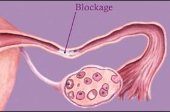

- Damage or blockage in the Fallopian tubes

- Hysterosalpingography to evaluate the condition of the uterus and Fallopian tubes

- Surgery to repair blocked or damaged fallopian tubes

₦54,000.00Blocked Fallopian Tubes Kit - Unblocked fallopian tubes, herbal treatment for tubal blockage,blocked fallopian tube treatment